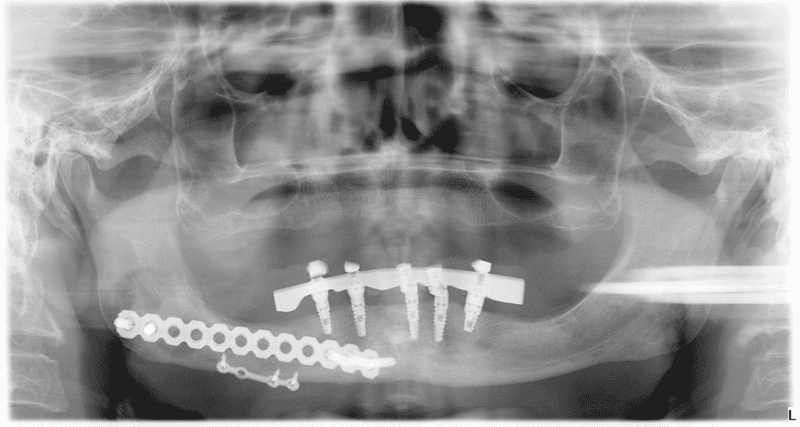

Dental Implants After a Motorcycle Accident:

X-ray Before Dental Implants:

X-ray of mouth After Implants: